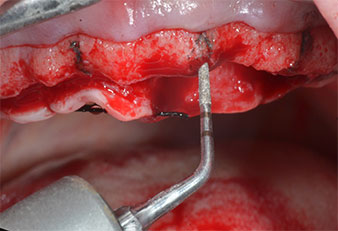

Marcador ultrasónico Piezomed

Fig. 3: La preparación con inserto marcador ultrasónico Piezomed I1 se realizó con movimientos hacia arriba y hacia bajo, paralelos al eje longitudinal del área de trabajo.